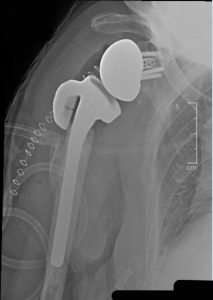

The Humeral Augmented Tray is the first implant of its kind. It replaces the greater tuberosity, a part of the shoulder that may be absent or deficient, fractured and/or reabsorbed due to disease. The HAT was designed to be used in combination with the Equinoxe Platform Shoulder System for reverse procedures and was designed to help improve joint mechanics and stability for patients with proximal humeral bone loss. This unique implant can also be used with an extension for more severe proximal bone loss cases.

The first surgeries with the Humeral Augmented Tray were performed last week in Florida by Bradley Schoch, MD, of the Mayo Clinic in Jacksonville, and design team surgeon Howard Routman, DO, of JFK Medical Center in Lantana.